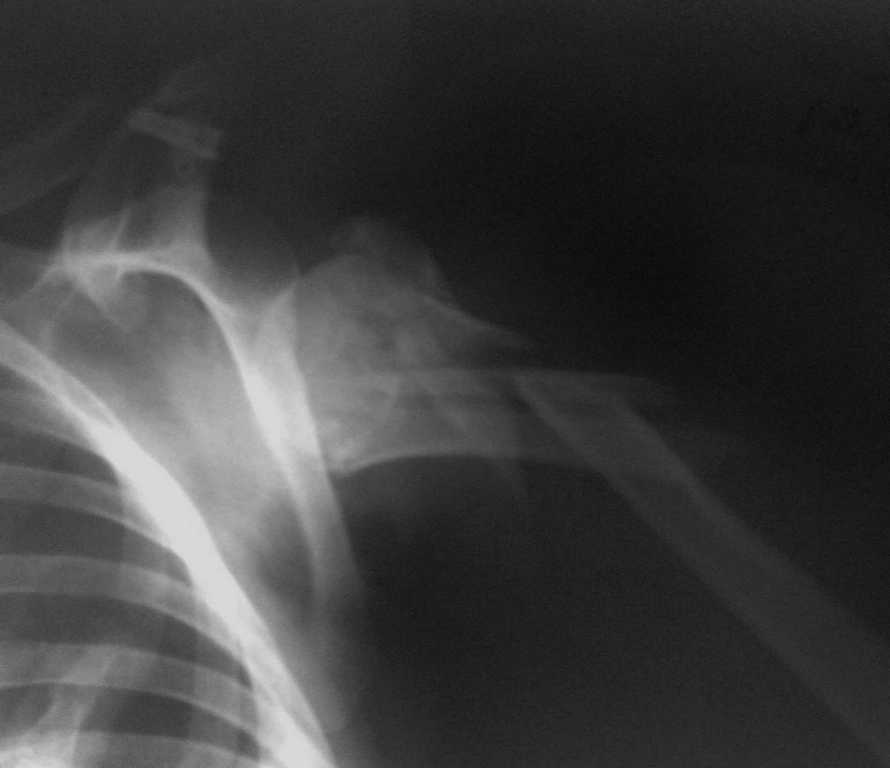

Переломо-вывих проксимального отдела плеча

Пациентка, 51год, автодорожная политравма: закрытый двойной перелом левого бедра (оперирован - Биос),полный внутрисуставной перелом проксимального отдела левой голени (будет синтез LCP PLT на предстоящей неделе), переломо-вывих проксимального отдела правого плеча. Травма от 08.01.2009

Александр, наверное низкое качество снимков вас дезориентировало. Имеет мество перелом головки плеча на уровне анатомическойт шейки, со смещением большого бугорка.Конечно, теоритически можно(по типу PFN) реконструировать проксимальный отдел плеча...... я склоняюсь к протезированию на ревизионной ножке(200мм) с синтезом отломков(осколков)серкляжом на ножке протеза...........

Вариант, предложенный Александром, вполне жизнеспособен. Хотя для планирования одной рентгенограммы, конечно, недостаточно. Надо и

другие проекции и КТ.

Вопрос с эндопротезированием интересный, но перелома

анатомической шейки не видно, только хирургической, или даже дистальнее. Так что остеосинтез вполне уместен.

Перелома анатомической шейки, действительно, не видно. но один из промежуточных отломков явно проксимально простирается до этой самой шейки, что делает гвоздь не очень хорошей опцией.